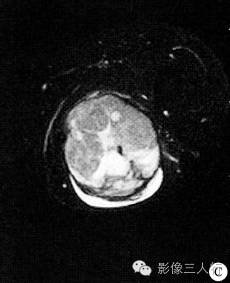

影像诊断:左大腿肌肉间隙占位性病变,考虑软组织肉瘤,横纹肌肉瘤可能大。

病理诊断:瘤体血管丰富呈鹿角状分支,管腔不规则,管壁薄;瘤细胞呈卵圆形或短梭形,胞质少;细胞核呈圆形或卵圆形,染色深,核分裂易见;瘤细胞围绕血管分布;免疫标记提示瘤细胞中度增殖。病理诊断为恶性血管外皮瘤。